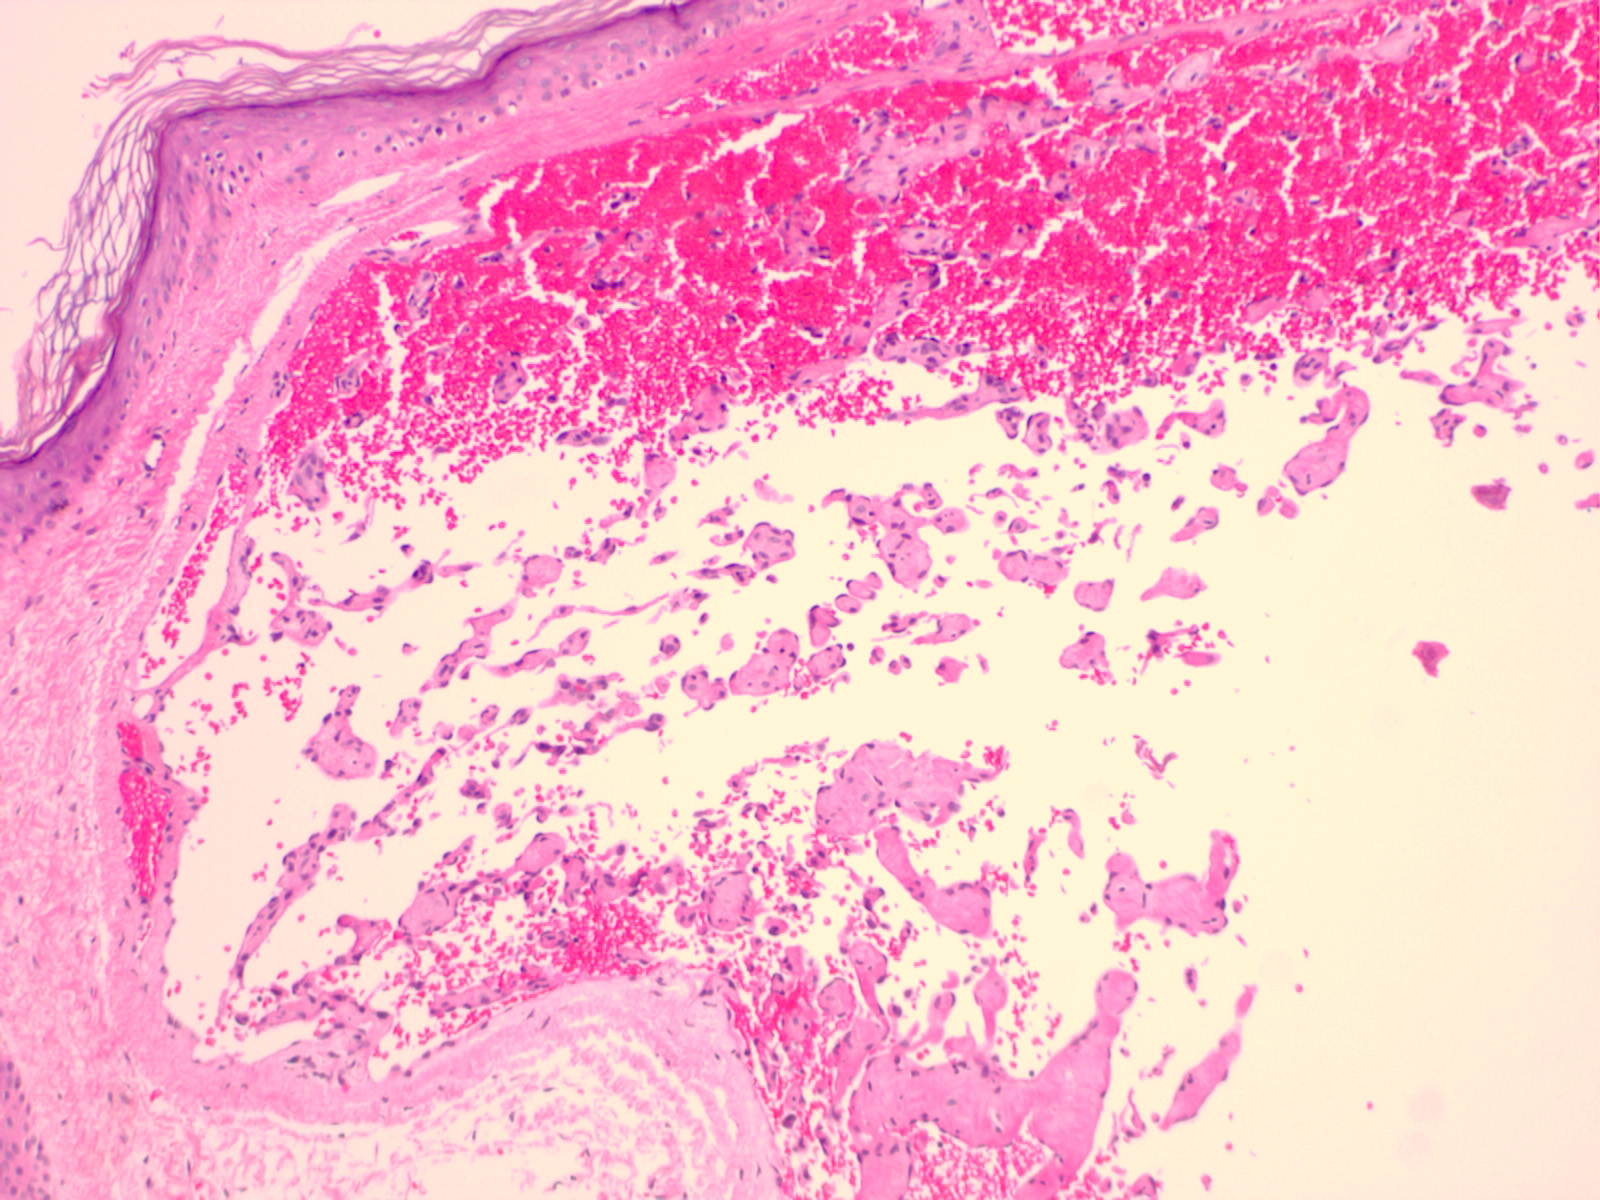

masson_tumor